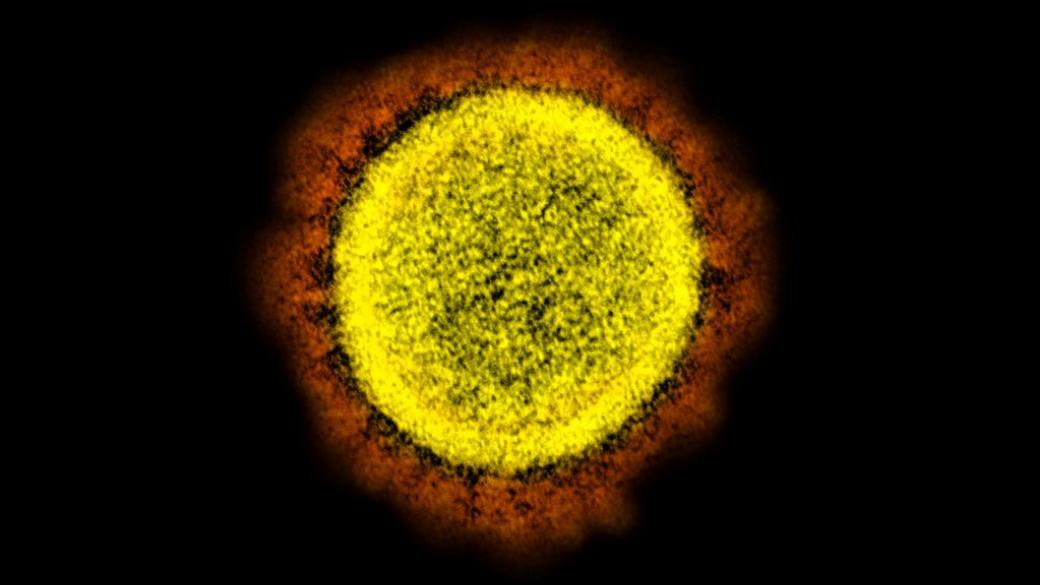

Ученые показали, как выглядит COVID-19 под микроскопом

Американские ученые показали, как выглядит вирус COVID-19 под микроскопом. Снимки предоставлены Национальным институтом аллергии и инфекционных заболеваний США.

Изображение вирионов SARS-CoV-2, разрастающиеся в клетке человеческого организма удалось получить с помощью просвечивающего электронного микроскопа. Снимки раскрашены с использованием специальных программ и Photoshop.

На фотографии можно увидеть вокруг вируса отростки, напоминающие солнечную корону, отчего коронавирус COVID-19 и получил свое название.